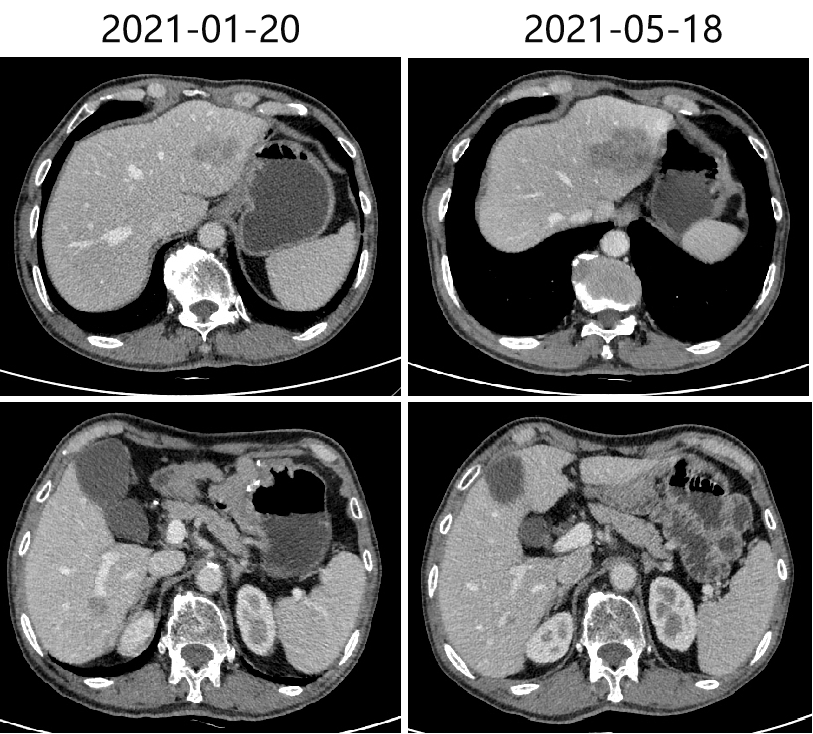

2020-10-30、2021-01-20 复查CT,疗效评价为SD。

2021-05-19头胸腹盆CT,提示双肺多发结节,较前(2021-01-20)大致相仿,考虑转移灶可能;肝左叶占位,考虑转移,较前增大;肝右后叶强化灶考虑转移,较前新增。

肺:肺多发结节,较前(2021-01-20)大致相仿,考虑转移灶可能。

肝:肝左叶占位,考虑转移,较前增大;肝右后叶强化灶考虑转移,较前新增。